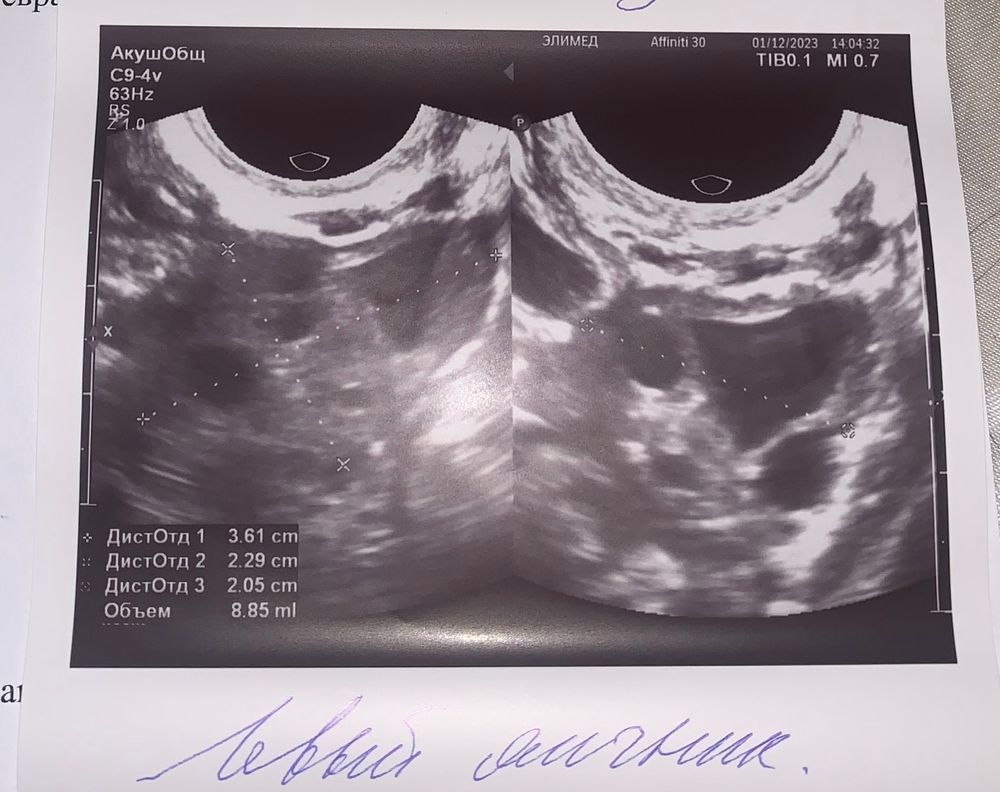

врач какой-то странный, толком ничего не смог объяснить( . Мне нужно было знать, что была овуляция. И в каком яичнике. (Я чувствовала боль в правом) врач сначала сказал - в левом. А может и в правом 🤷🏼♀️ я говорю - а желтое тело? Он мне куда-то тыкнул пальцем, типо вот тут ЖТ видимо. И все 😕 я вообще ничего не поняла…. Девочки, я прошу момощь зала🙏🏻 Вам что-то понятно по узи ?